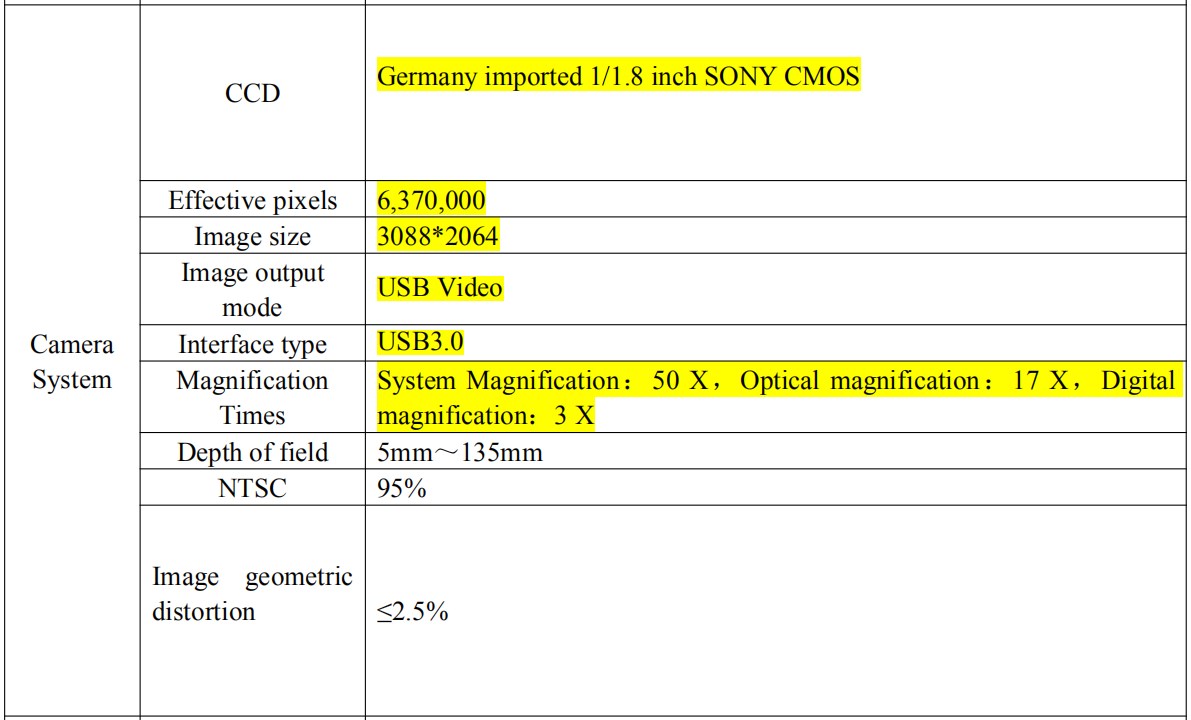

Camera system technical parameter